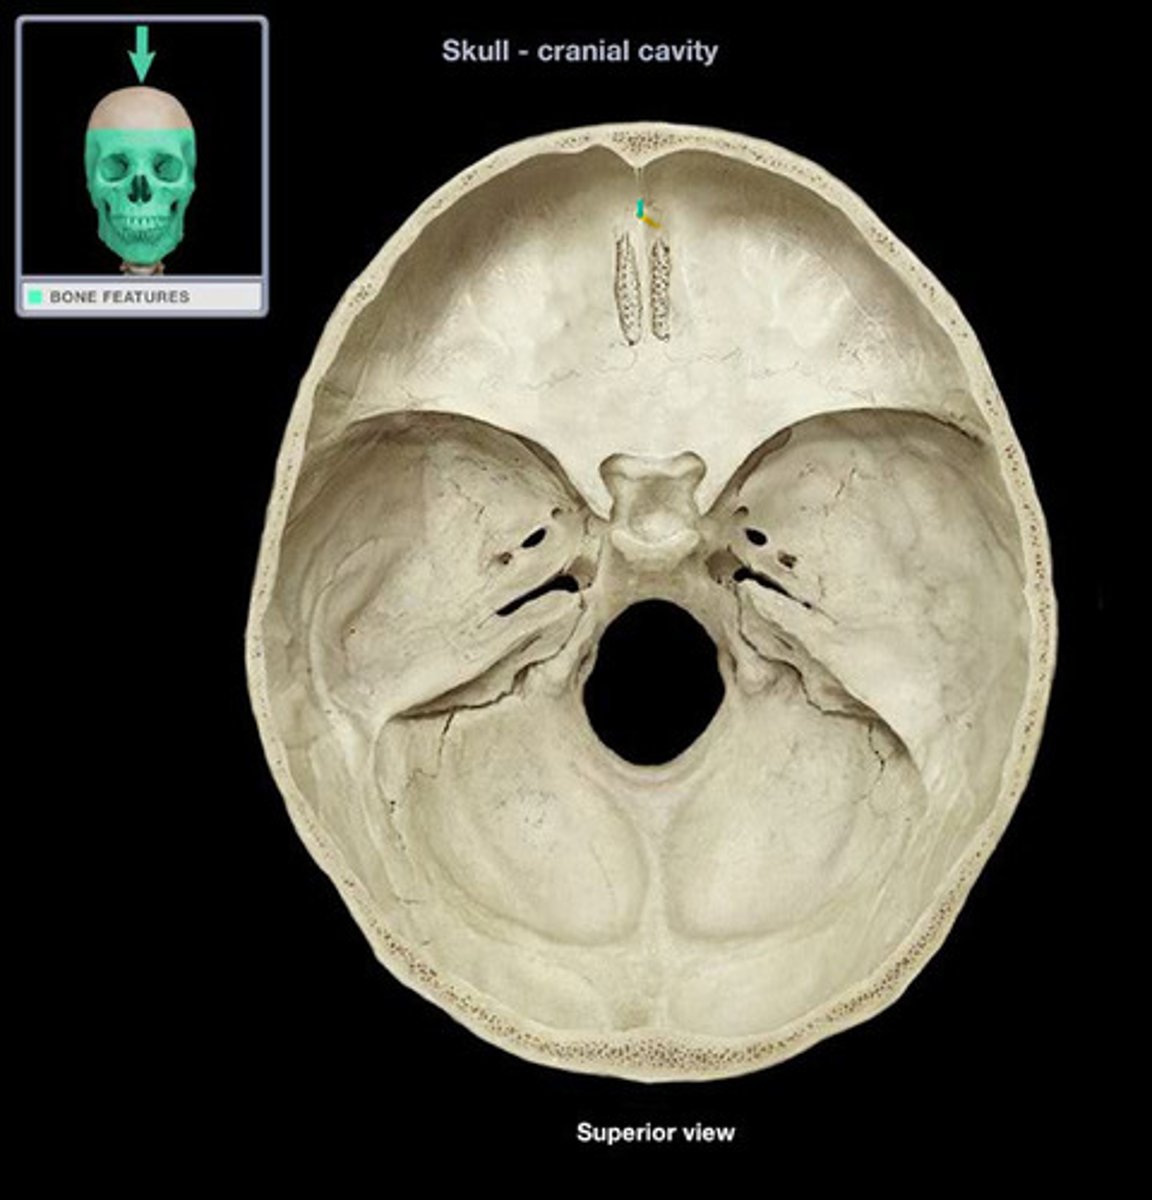

foramen cecum

hole that is typically closed, but may transmit the emissary vein

cribiform foramina

hole that transmits olfactory nerve filaments

ethmoidal foramina

hole that transmits ethmoidal nerves, arteries, and vessels